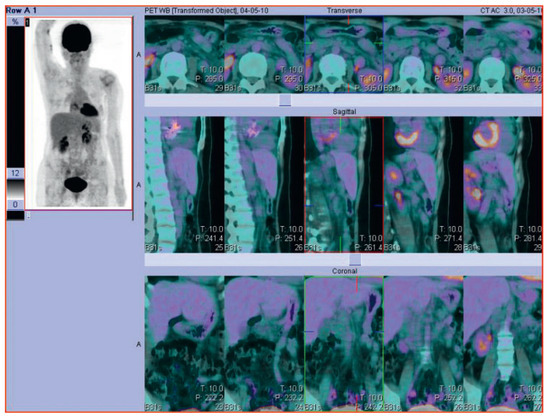

Der 70-jährige Patient wurde uns zugewiesen zur stationären kardialen Rehabilitation bei St. n. mechanischem Aortenklappenersatz wegen schwerer degenerativer Aortenstenose.[...]